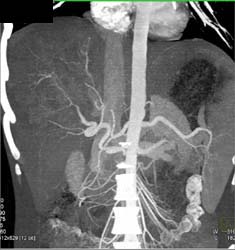

Large Varices